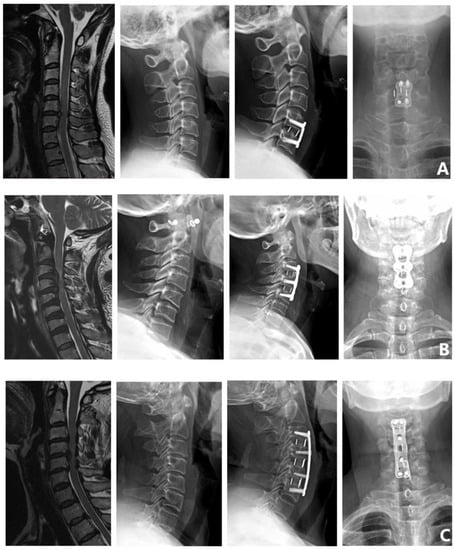

Surgical methods: ① Single-segment anterior cervical decompression and fusion (single ACDF). ② Double-segment anterior cervical decompression and fusion (double ACDF). ③ Three-segment anterior cervical decompression and fusion (three ACDF). ④ Anterior cervical corpectomy and fusion (ACCF). ⑤ Anterior cervical hybrid decompression and fusion (ACHDF). ⑥ Posterior cervical laminectomy (laminoplasty). ⑦ Posterior cervical laminectomy and fusion (laminectomy and fusion) (Figure 2).

Figure 2.

Surgical methods. (A) Single ACDF. (B) Double ACDF. (C) Three ACDF. (D) ACCF. (E) ACHDF. (F) Laminoplasty. (G) Laminectomy and fusion.